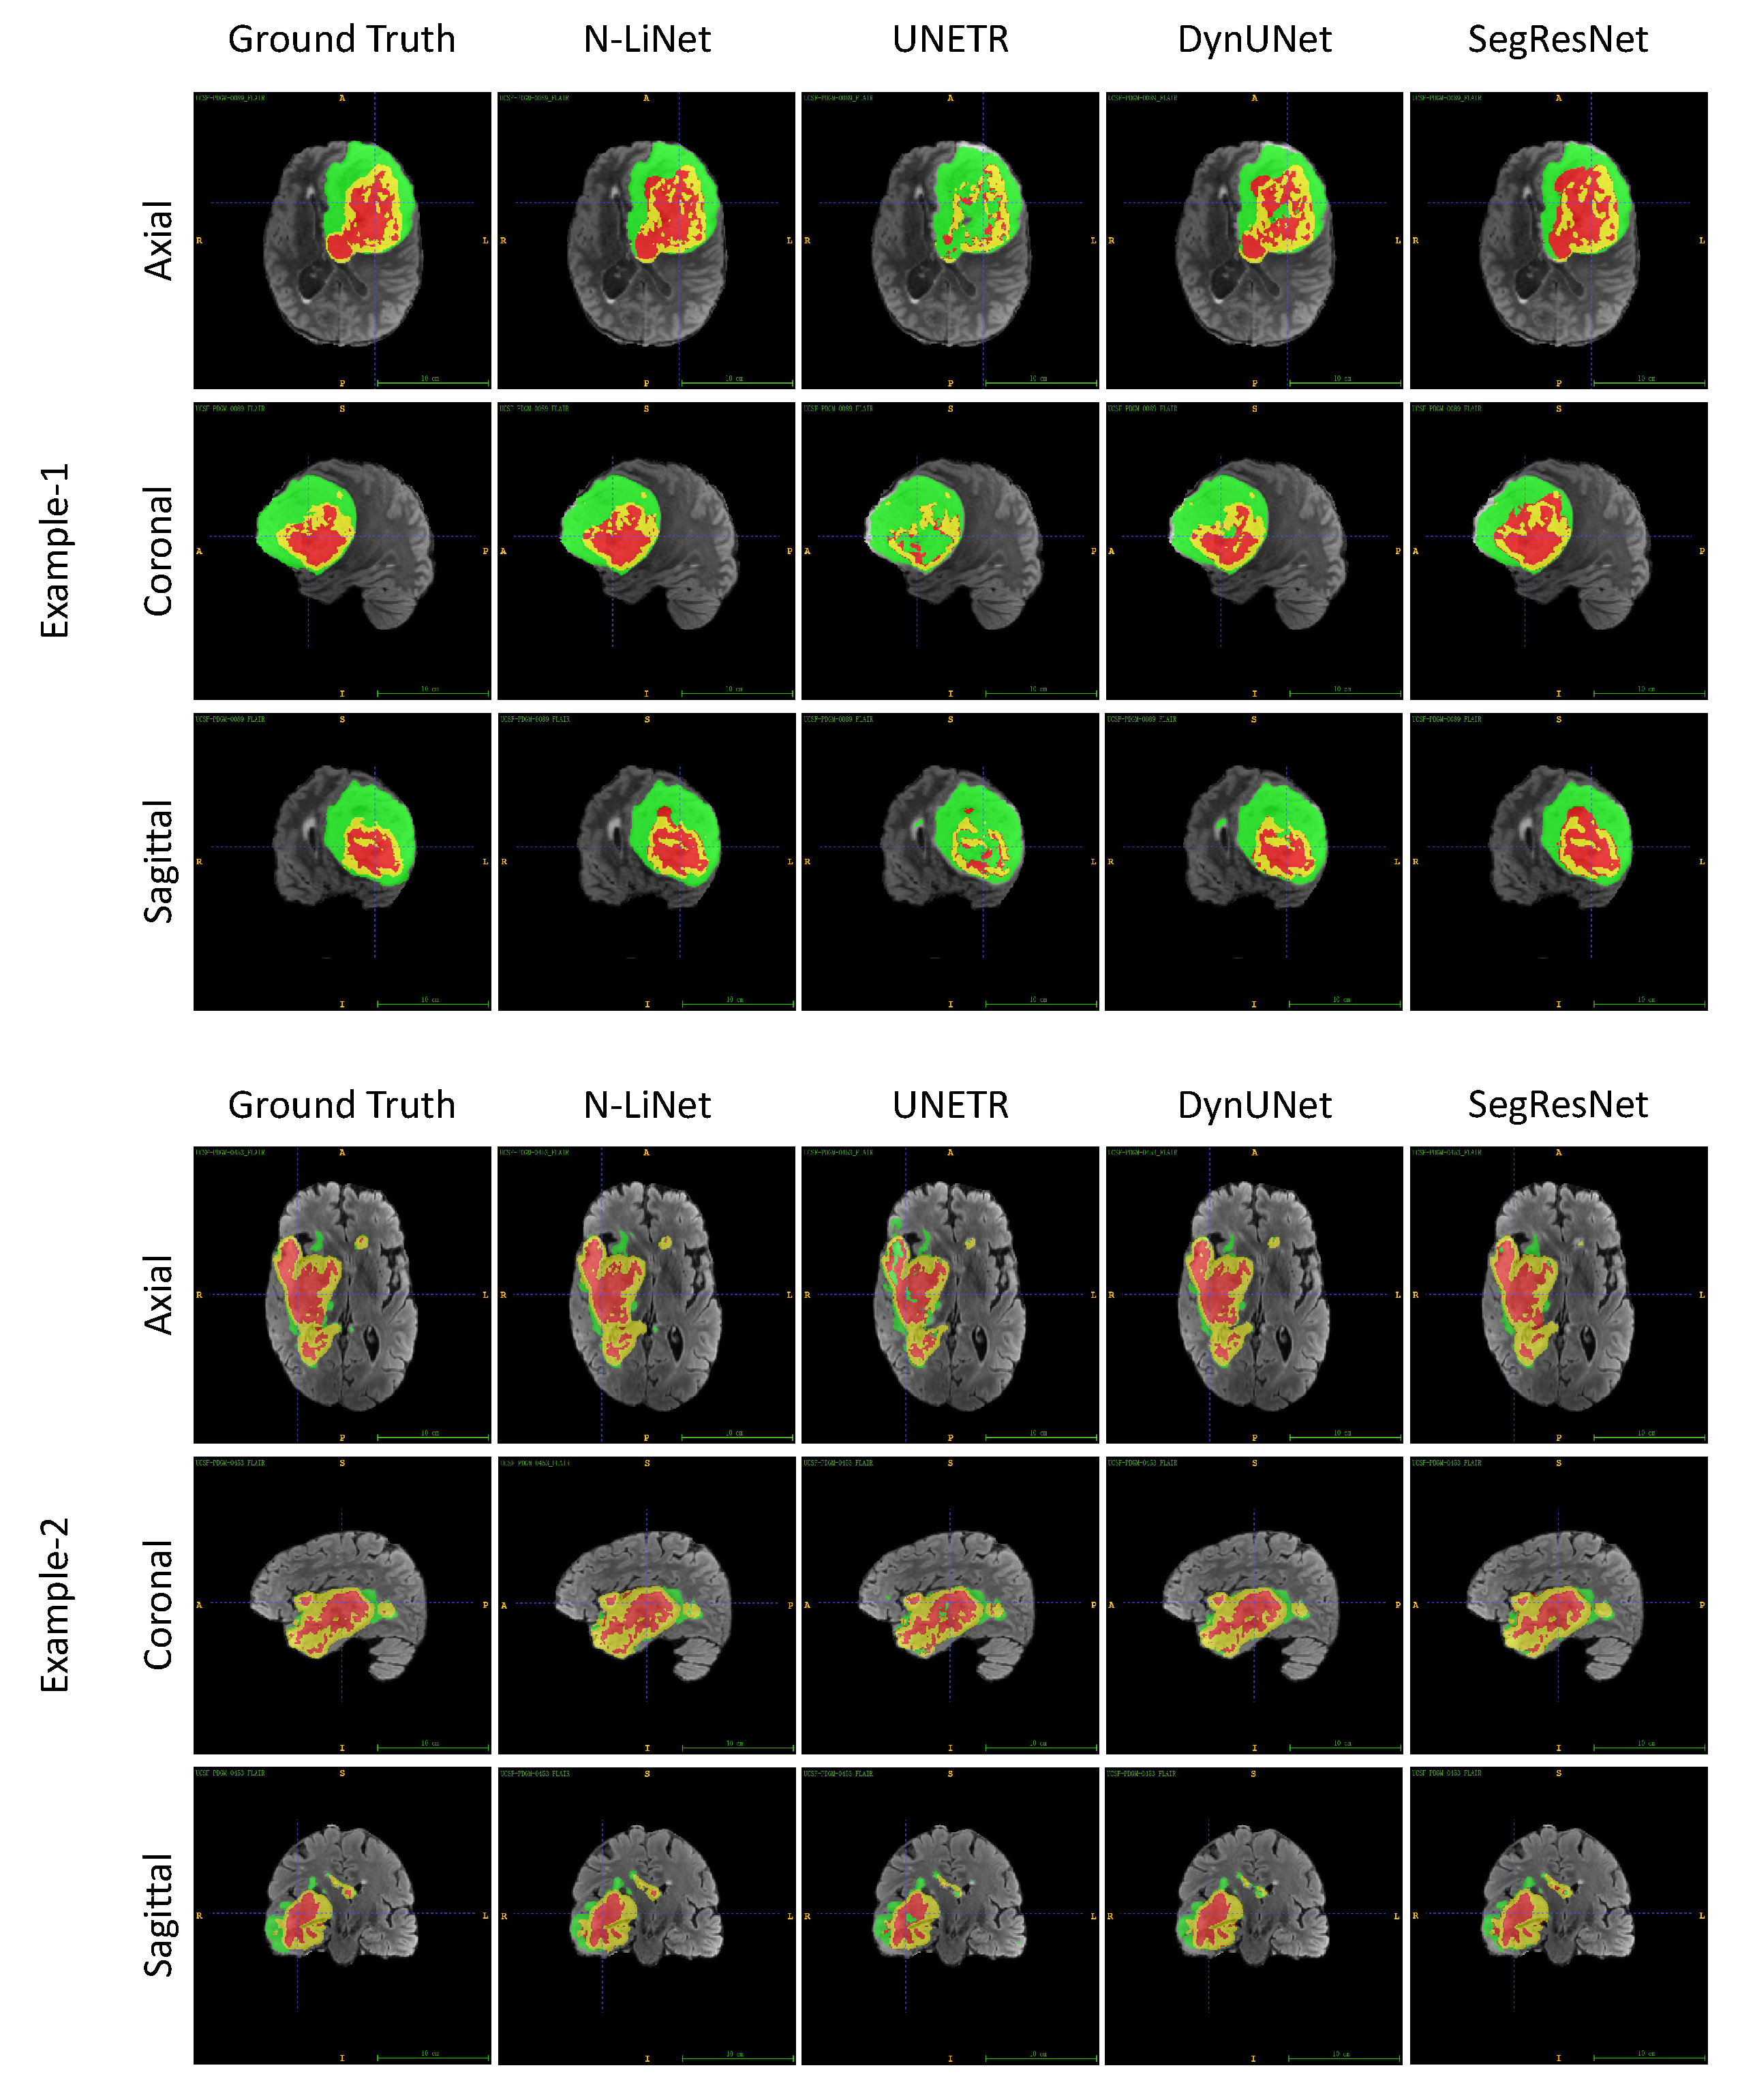

5.1. Segmentation Performance Comparison

5.1.1. Segmentation Metrics Comparison